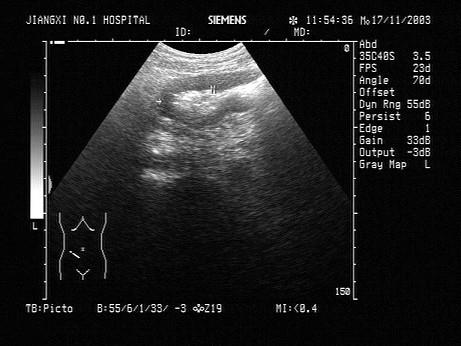

问题 患者,男,右下腹有压痛,时有腹泻。结合超声声像图,诊断是?(?)

选项 A.溃疡性结肠炎 B.结肠癌 C.阑尾脓肿 D.肠结核 E.肠梗阻

答案 B